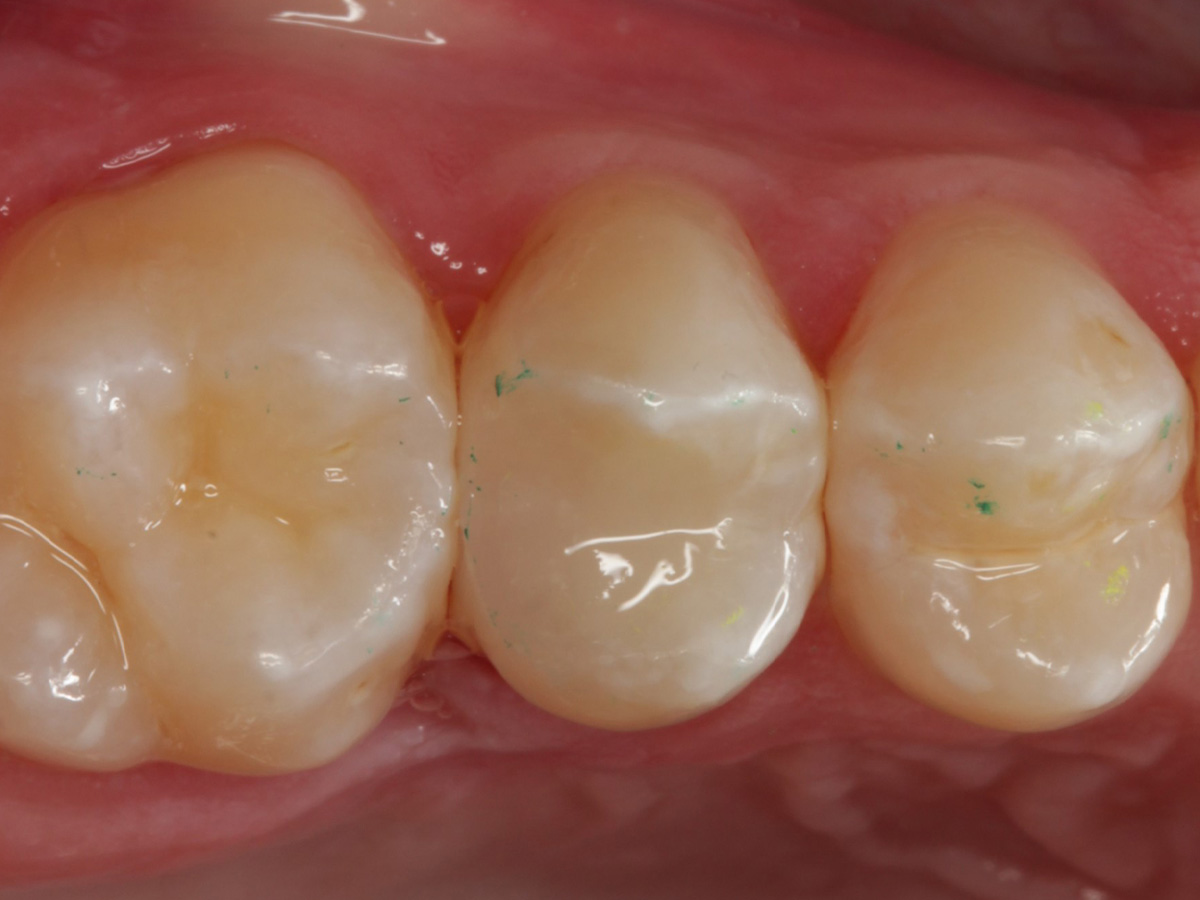

Abbildung 2

Intakte Kaufläche